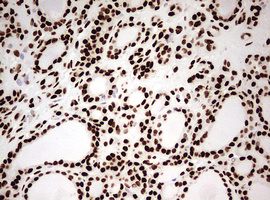

Immunohistochemical staining of paraffin-embedded Adenocarcinoma of Human ovary tissue using anti-HNRNPM mouse monoclonal antibody. (Heat-induced epitope retrieval by 10mM citric buffer, pH6.0, 120°C for 3min, M06017-2)